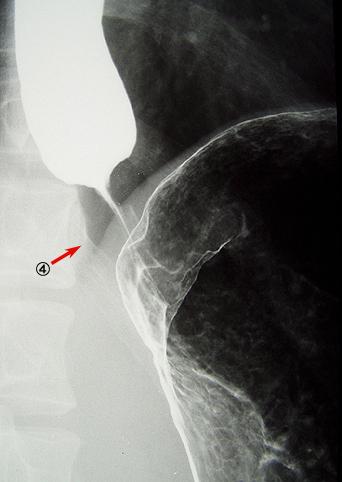

A case of type 3 advanced gastric cancer with multiple intramural and extramural metastases.

[ Image ID:9020 ]

Malignant epithelial tumor/Signet-ring cellcarcinoma

Location

Esophagus/Lower third

X-ray

20 - 24